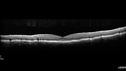

Foveal hypoplasia - aplasia494 viewsSD OCT shows persistent plexiform layers in the center of the macula

EXTENDED HPI: He is having some trouble seeing his gadgets (like his watch). He was diagnosed with morning glory syndrome at about 3 yeras old. This last visit you saw fluid under the retina and asked him to come here. The vision is a little worse.

VA OD: Dcc20/40+2 NccJ2-2

VA OS: Dcc20/25-2 NccJ1-2Dec 20, 2018